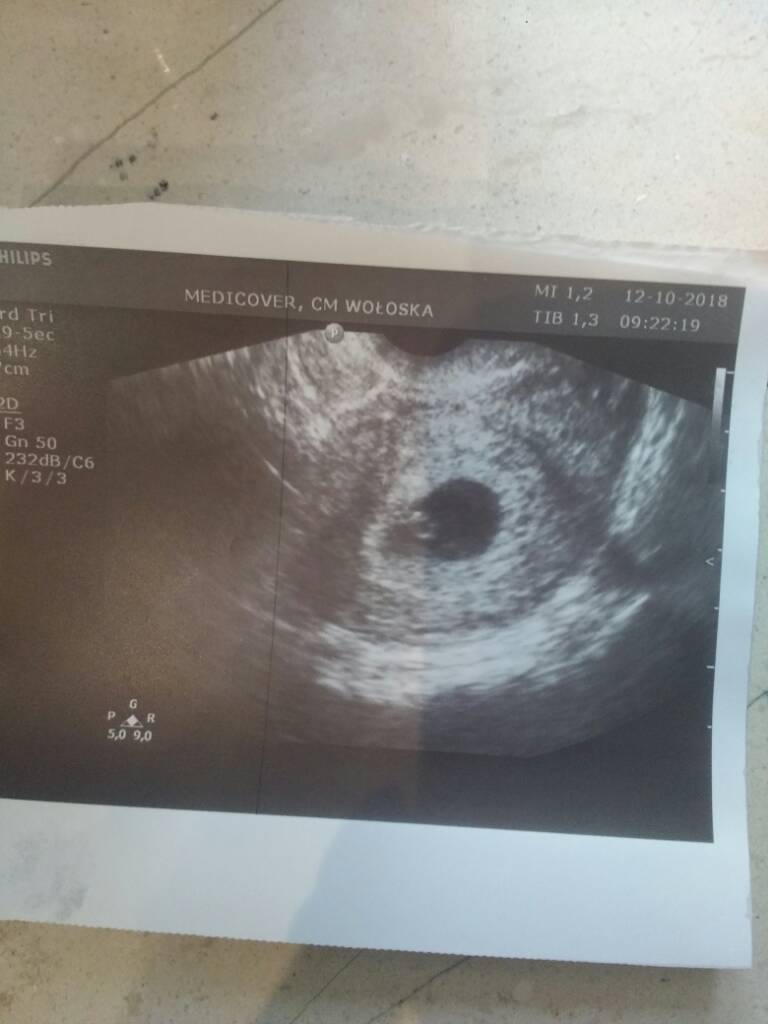

A pomógł ci na nietrzymanie moczu? Ja po porodzie miałam problem przez krótki czas ale w samej poprzedniej ciąży to był armageddonTo może właśnie spróbuj się zapisać do jakiegoś dobrego fizjo. Na prawdę fizjoterapia może bardzo duzo pomox. Ja tym razem planuje chodzić do fizjo po porodzie bo jak sobie przypomnę to nietrzymanie moczu itp to mnie skręca [emoji6]Ja 11+2 dopiero[emoji6] w poniedziałek dopiero mam prenatalne i test pappa[emoji6] w pierwszej ciąży pappy nie robiłam a teraz dostałam skierowanie z medicover więc skorzystam [emoji6]